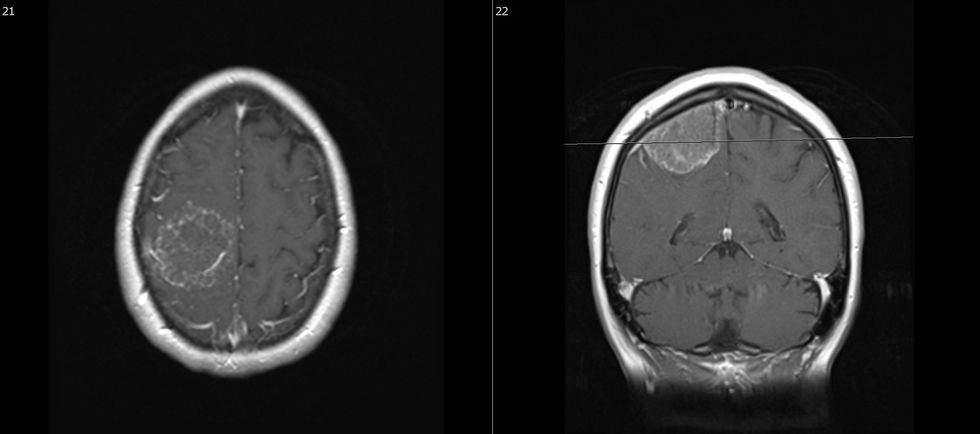

Gliomat lindin nga qelizat mbështetëse të Sistemit nervor qendror dhe janë tumoret primare më të zakonshme të indit të trurit. Sot, gliomat klasifikohen kryesisht sipas aspekteve patologjike molekulare. Vetëm astrocitomat pilocitare (WHO – OBSH – Organizata Botërore e Shëndetësisë) të shkallës 1 janë të shërueshme, të gjitha gliomat tjera recidivojnë me kalimin e kohës. Prandaj, qëllimi i trajtimit është zgjatja e jetës me cilësi të lartë. Opsionet e trajtimit janë operacioni neurokirurgjik, rrezatimi, terapia medikamentoze dhe trajtimi me “tumor-treating-fields”.

Qëllimi i operacionit është zvogëlimi sa më i madh i masës tumorale pa shkaktuar dëme neurologjike. Sidoqoftë, një "resekcion i plotë" biologjik është i pamundur. Në shumicën e rasteve pas operacionit trajtimi vazhdon me rrezatim dhe / ose terapi medikamentoze. Në rastin e tumoreve malinje (glioblastoma) është e mundur edhe terapia me fusha të terapisë së tumorit (“Tumor-treating-fields”). Mitoza e qelizave tumorale të mbetura me këtë metodë pengohet nga një fushë magnetike e aplikuar në kokë vazhdimisht. Koha deri në recidivimin e tumorit ose koha e mbijetesës varen nga shumë faktorë, ku biologjia e tumorit luan një rol vendimtar.